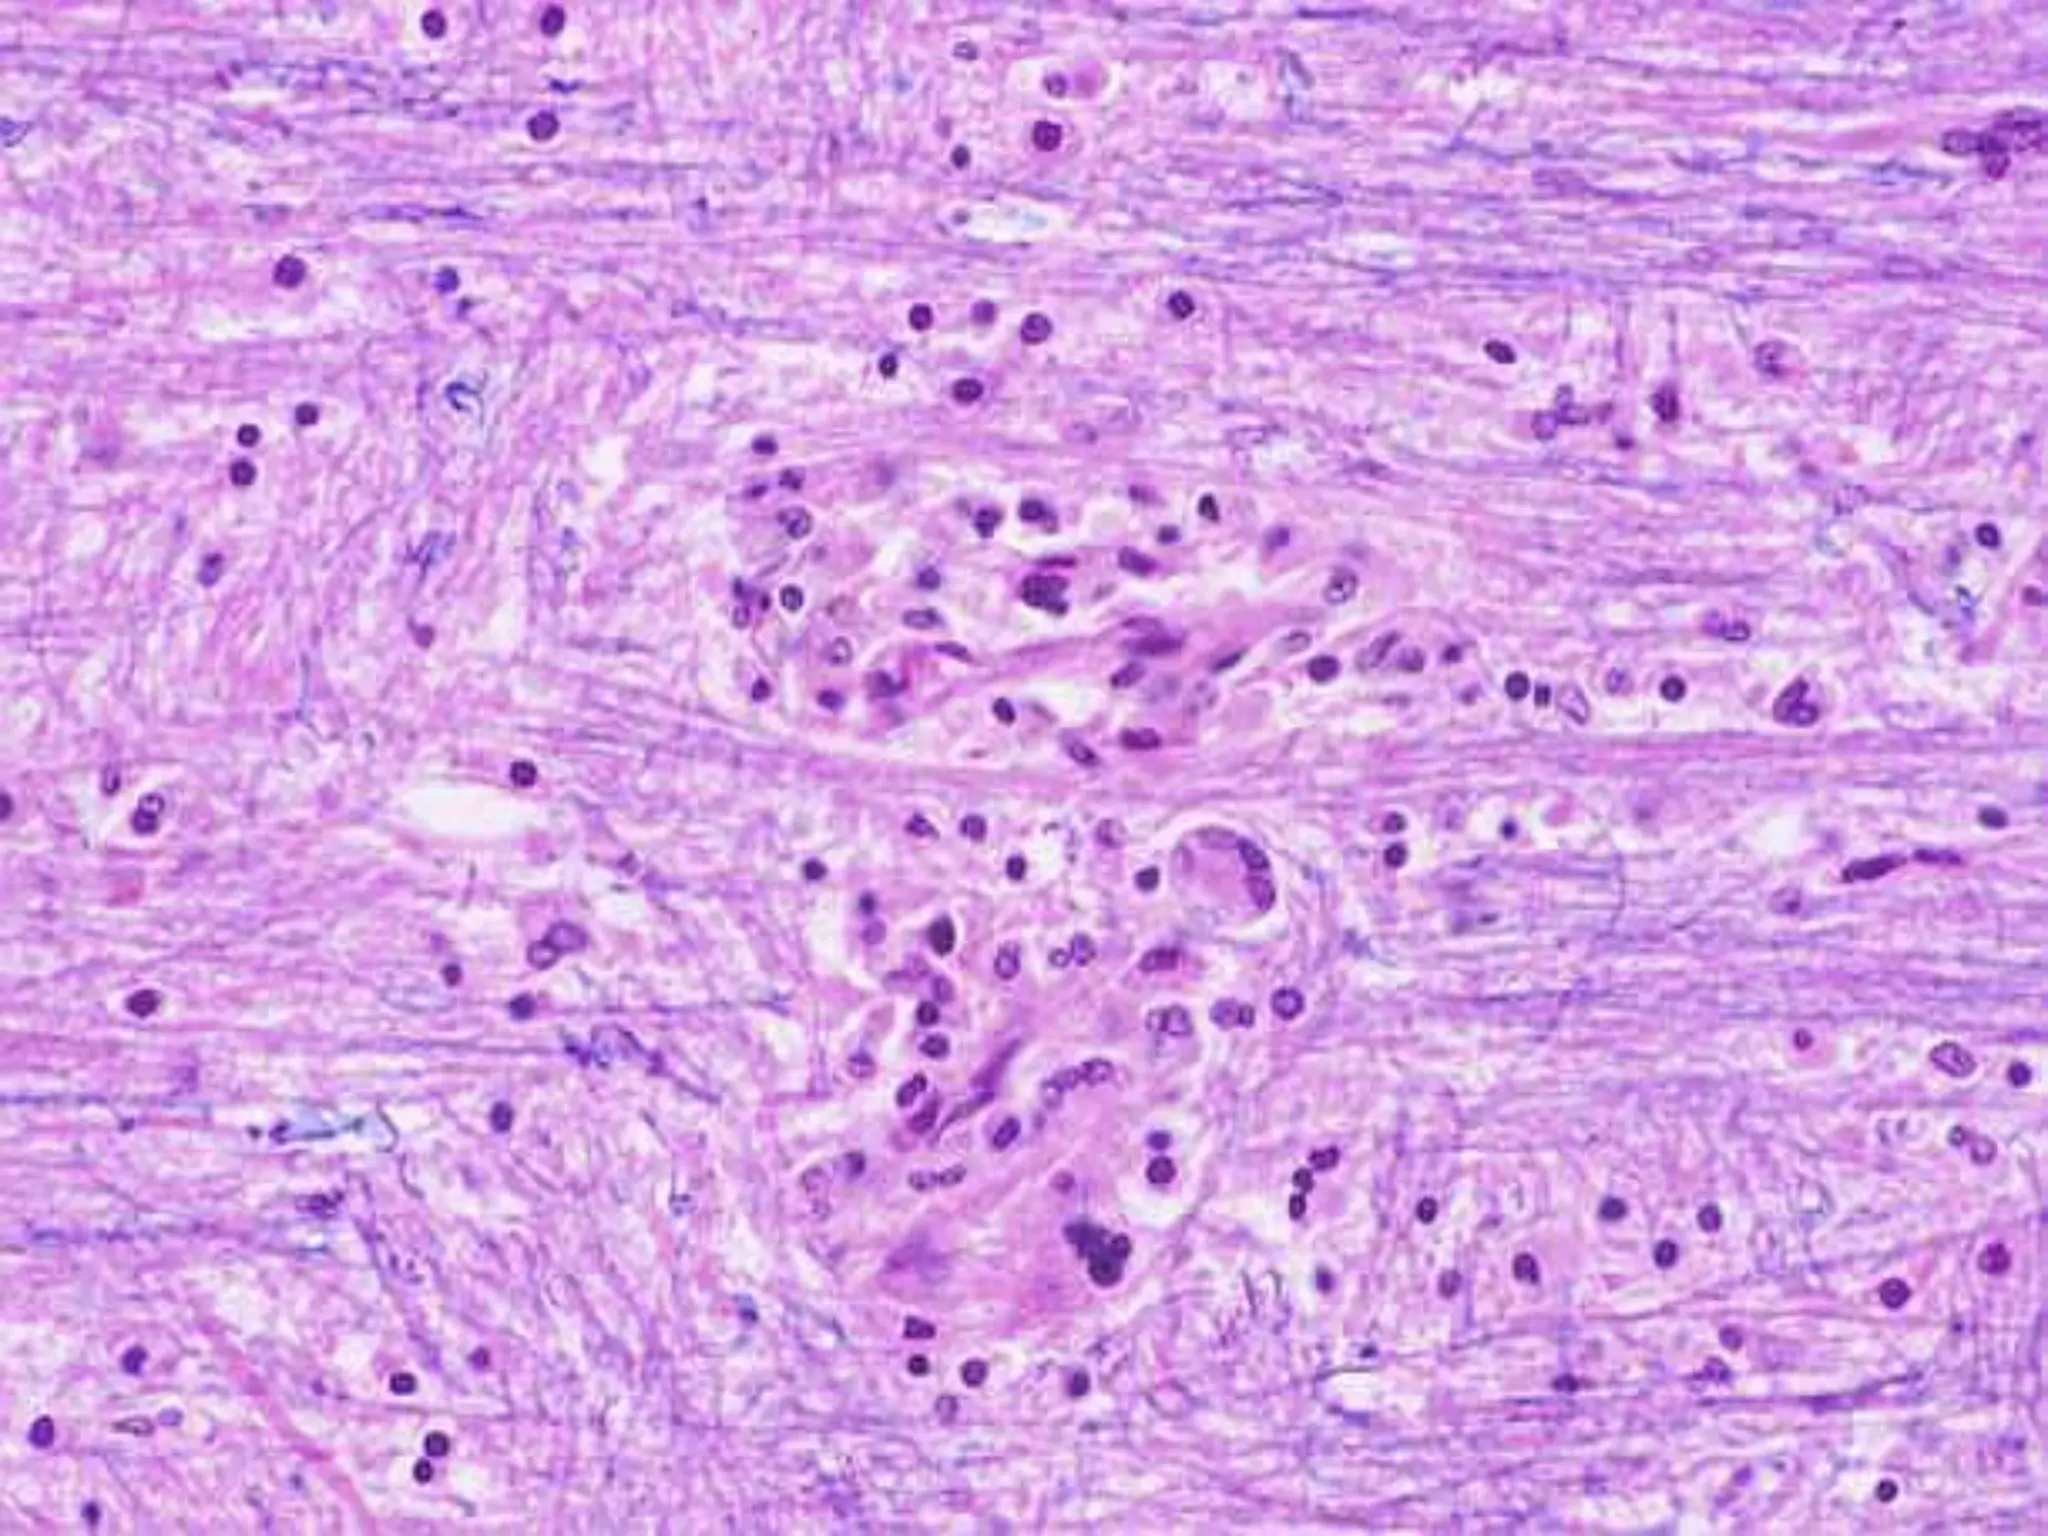

BRAIN ABSCESS

Gross: discrete, liquefactive necrosis,

MICROSCOPY

 Exuberant granulation tissue with

neovascularization around necrosis  edema,

 Fibroblasts of vessels  collagen of capsule.

• 19.

Gross: discrete, liquefactivenecrosis, fibrous capsule, edema.

MICROSCOPY  Exuberant granulationtissue with neovascularization around necrosis  edema,  Fibroblasts of vessels  collagen of capsule.